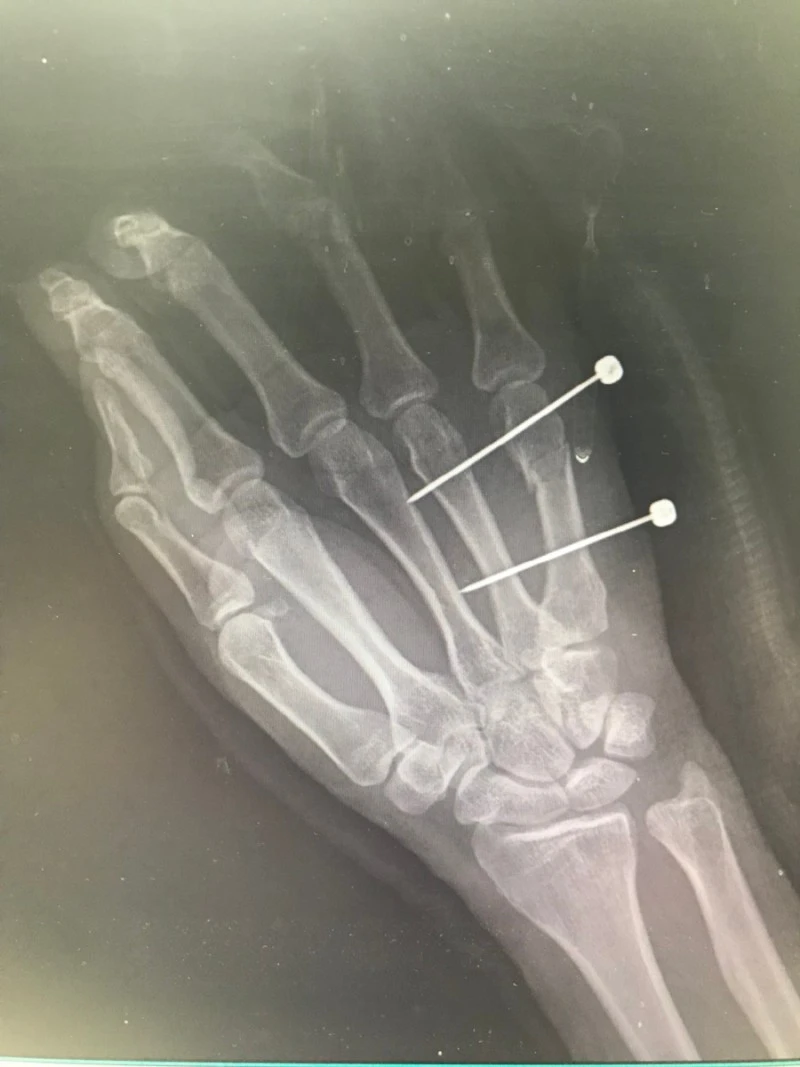

한동안 오른손에 핀 박고 지낼 때, 지리멸렬한 통증을 잡으려고 디클로페낙을 매일 응급실에서 맞곤 했습니다.

따끔한 일침이 두려워 엉덩이에 힘을 주면, 주사가 더 아픈 거 아시죠? 주삿바늘 앞에 초연한 엉덩이처럼, 힘을 빼면 삶은 더 경쾌하고 유연해집니다.